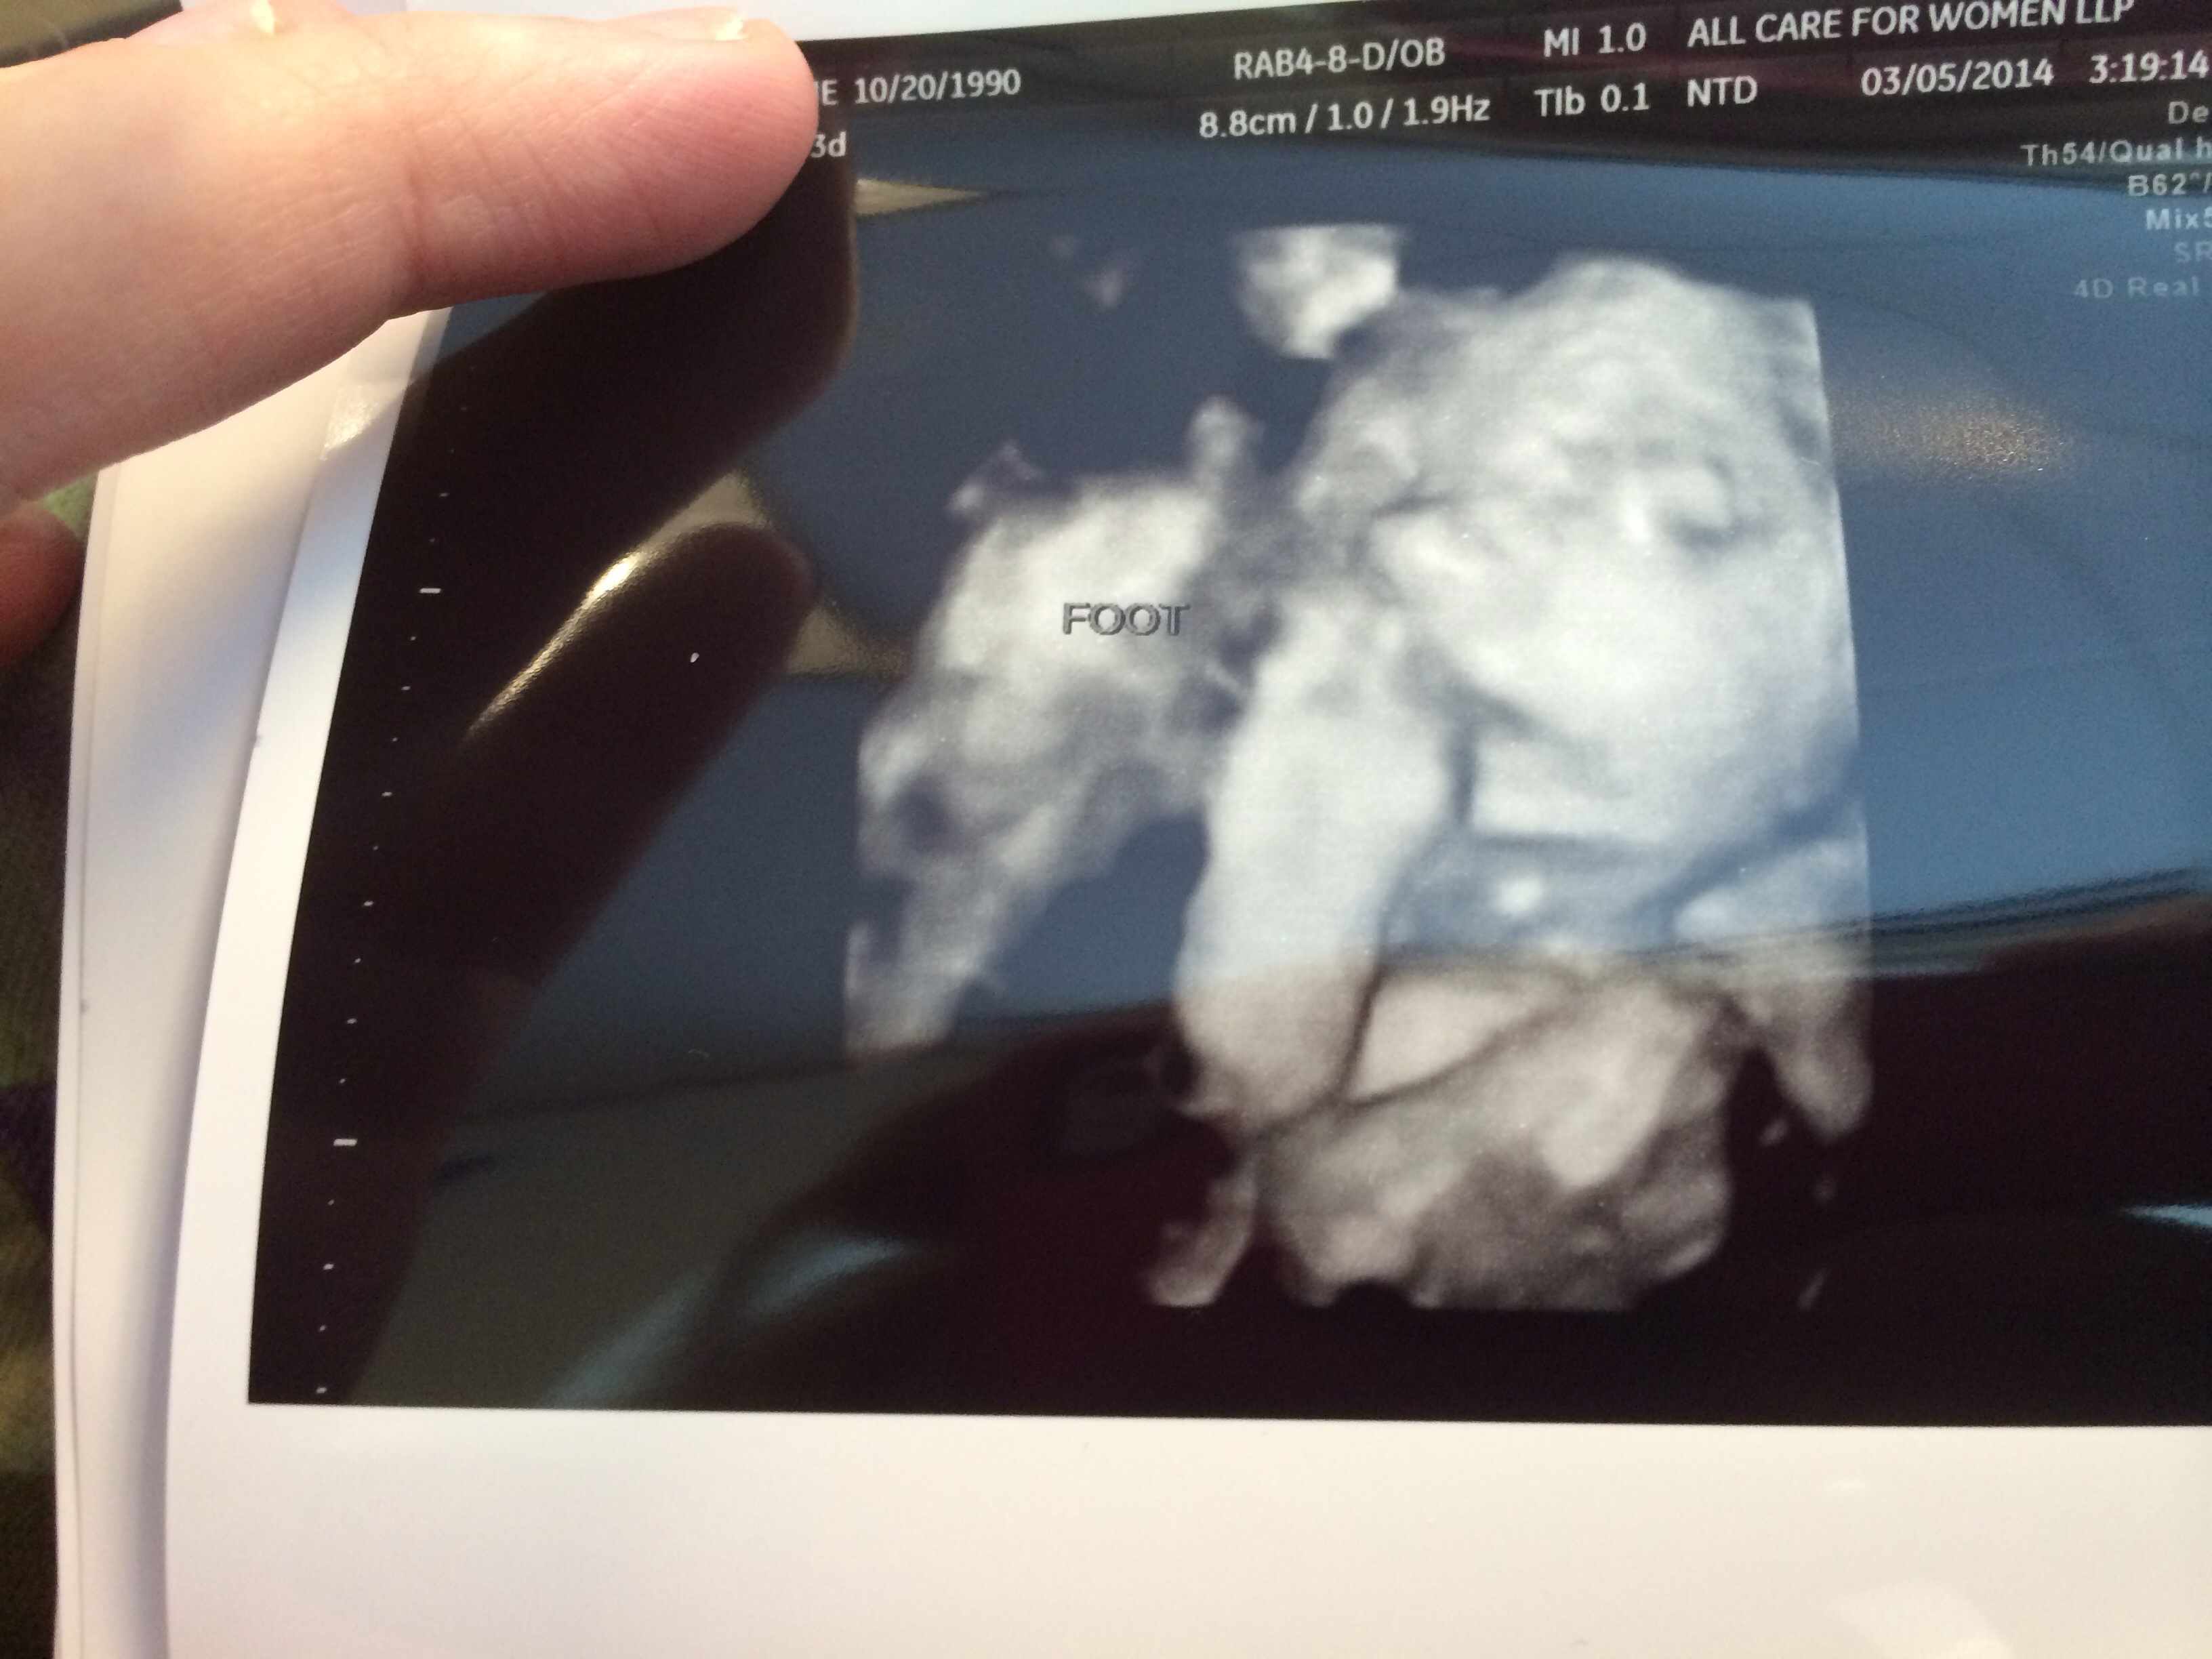

• Appt went great miss scotlyn is right on target weighing in at 1 pd 6 oz and I was able to get some good 3 d shots

Good news is that my baby girl is perfect in every way. She's breech, had her head down, hands in front of face, feet over her head, but we did manage to get a couple of good shots:

imageimage